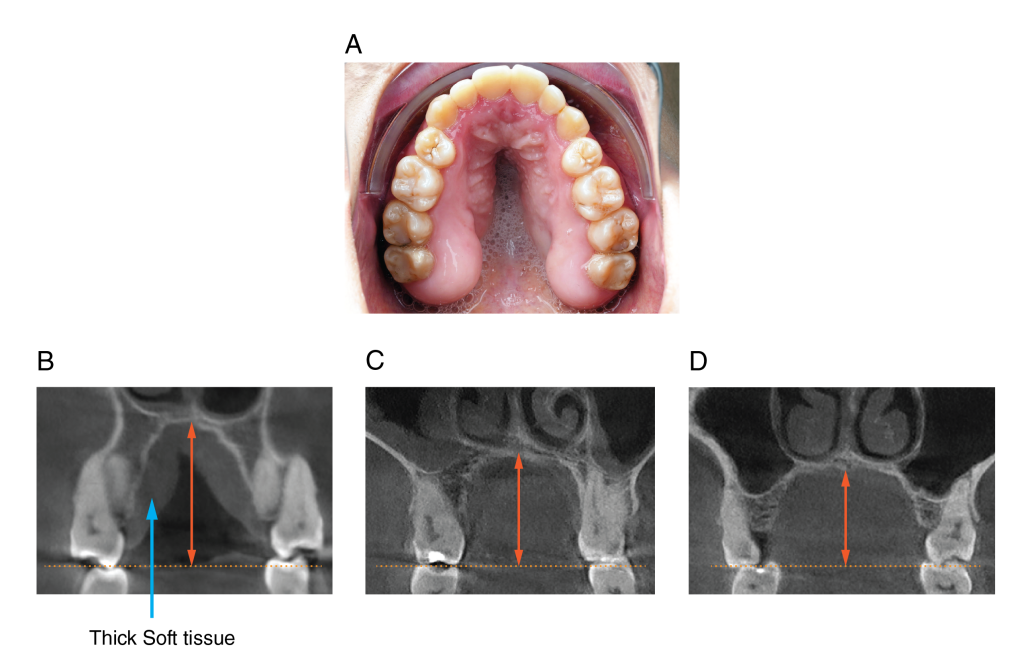

Figure 4: Intraoral and CBCT of the Palate of the NM patient. Palate demonstrates a severe soft tissue cleft, uncommon in most malocclusions (A). CBCT demonstrated a thin palate (B); however, no cleft in the bone was observed. The palate was significantly deeper than that of the matched open bite (C) and the matched control patient (D).Â